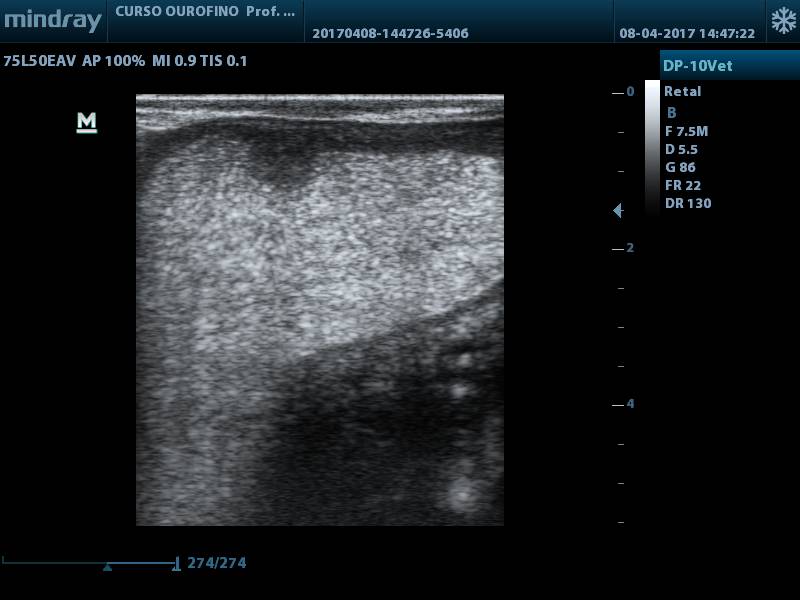

Após 30 dias pós-parto (D+30), durante exame de rotina realizado pelo médico-veterinário responsável, foi notado acúmulo de líquido no útero, palpação retal, porém, sem alteração dos parâmetros fisiológicos e hemograma dentro dos padrões esperados. No exame ultrassográfico foi confirmada a presença de substância com característica hiperecóica no lúmen uterino (fig. 1) e corpo lúteo (fig. 2).

Figura 1.